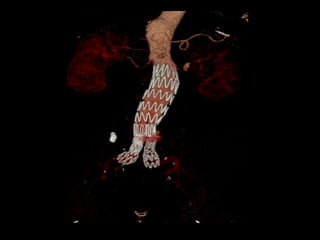

Iliac branch graftIliac branch graft

http://www.perfuse.netVascular surgery @ Tallaght